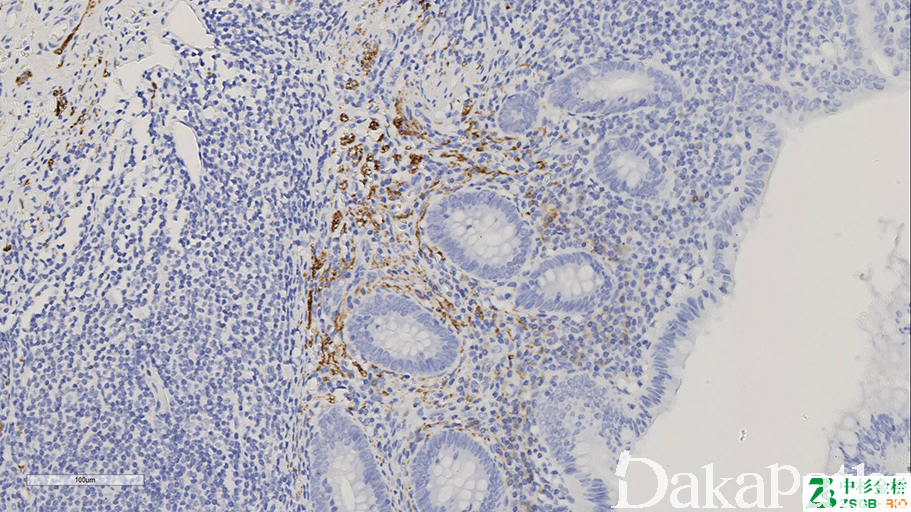

NSE

标记神经元、神经内分泌细胞及其肿瘤。

信号定位: 胞质